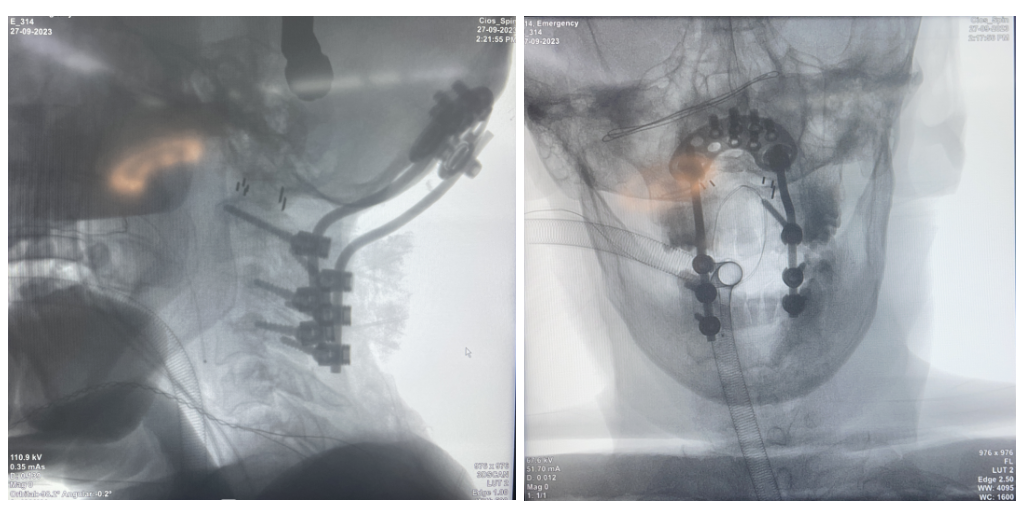

病例一

簡介:

友商枕頸融合術(shù)后1年2個(gè)月拔釘,使用我司枕頸產(chǎn)品翻修。

患者枕骨區(qū)域骨質(zhì)薄,使用φ4.5×5mm螺釘6枚,術(shù)后隨訪效果良好。